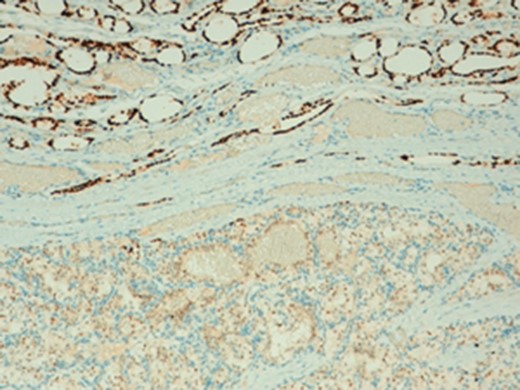

In microscopic evaluation the tumor had a predominantly ‘clear cell’ morphology, typical of RCC as shown in Figs 2 and 3.

Normal thyroid tissue on the lower left corner; clear cells in the upper right quadrant.

The histologic diagnosis was aided by the use of immunohistochemistry which was positive for PAX8 (Fig. 4) and CD10, and negative for thyroid transcription factor 1 (TTF-1) (Fig. 5), vimentin and chromogranin.